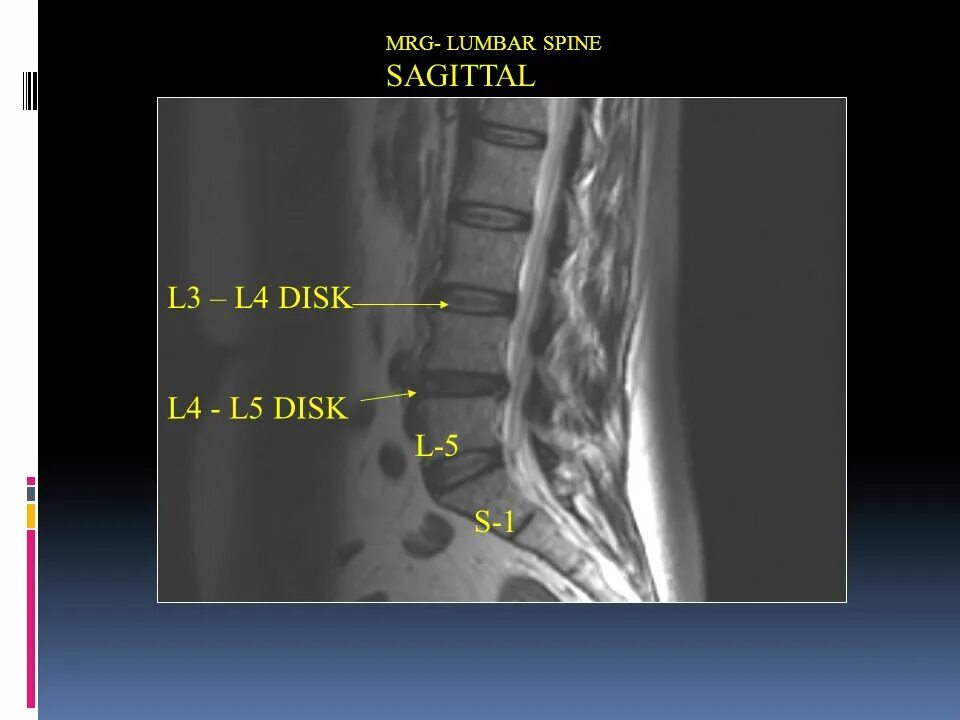

L 5 3